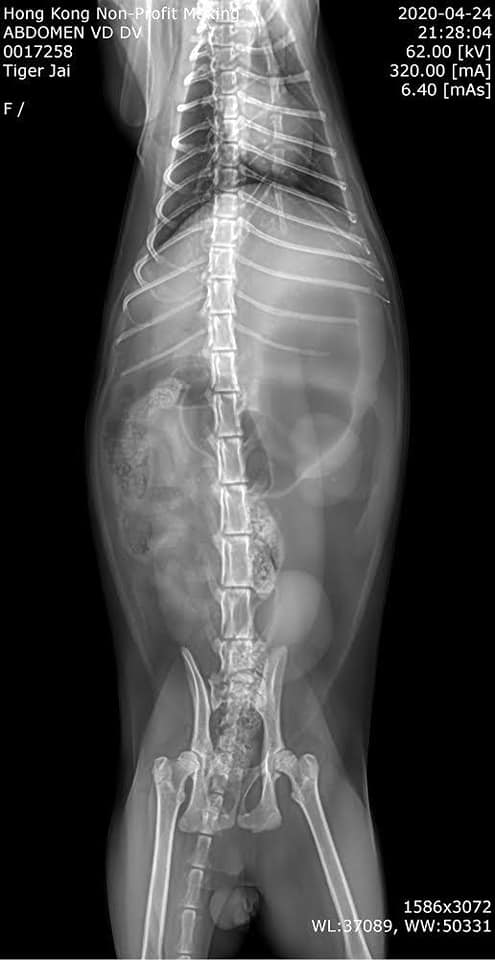

▼獸醫檢查後發現Tiger不僅外表有創口,還有異食的狀況,經常吞吃不該吃的東西,要做人為治療。治療半年多後,Tiger才恢復健康,現在已經變成一隻精力十足、活潑可愛的家貓,跟以前完全不同了。